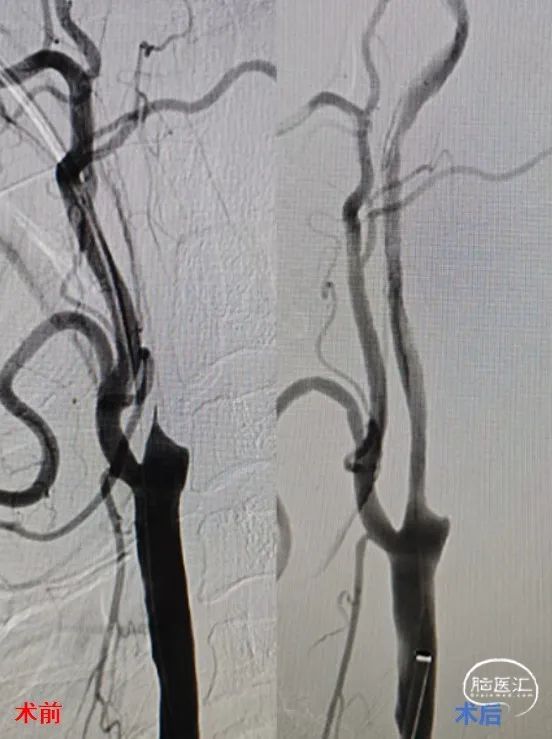

DSA造影(2024.11.07)

右侧颈内动脉起始段闭塞,动脉晚期可见颈动脉颅内段浅淡显影。

术后成形良好

术后影像(2024.11.12)